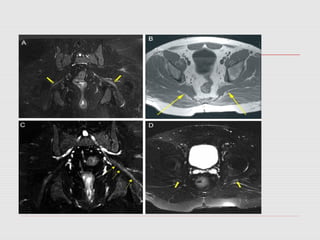

 In fewcases when patient showed strong clinical signs and was not responding to physiotherapy, we asked for an MRI.

No role ofX-rays, Neurophysiological Tests are consistent with Peroneal Division of Sciatic Nerve. Nerve conduction shows delayed F&H waves reflex. MRI is diagnostic